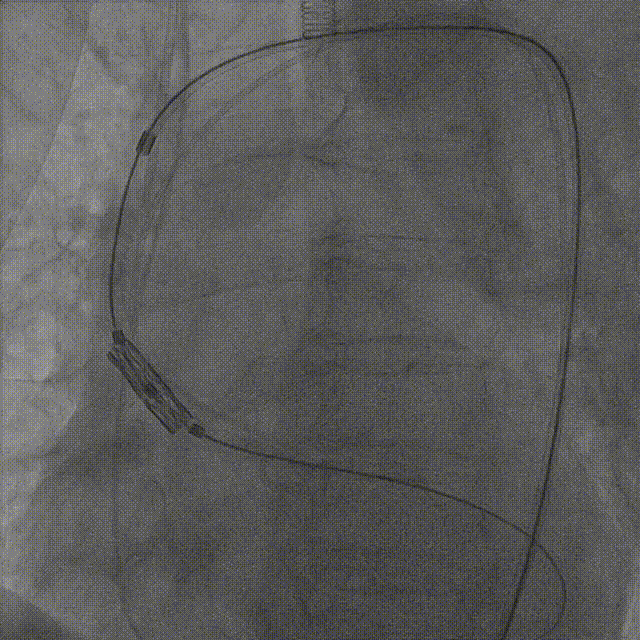

患者取平卧位,常规消毒铺巾,穿刺右侧颈内静脉,置入临时起搏器。主动脉根部造影显示主动脉瓣重度狭窄,钙化明显,开放明显受限,直头导丝跨瓣到左室,左心室及升主动脉测压,峰值跨瓣压差达105mmHg;

交换超硬导丝至左心室,经右股动脉送入预装有Myval™ 26mm瓣膜的输送系统,成功完成跨瓣操作到达主动脉根部,调整释放深度;

参考术前CT测量值,调整瓣膜至释放前最佳高度,缓慢释放近1/3长度时复查主动脉根部造影,确认瓣膜高度适合,临时起搏180次/分,以80:20比例23±1mL快速释放瓣膜至瓣膜工作区完全打开,于标准位置释放瓣膜;

复查造影提示瓣膜固定良好,形态尚可,未见明显反流;复查超声提示瓣膜功能正常,平均跨瓣压差下降至5.01mmHg,未见明显瓣周漏;最后退出鞘管,缝合血管。